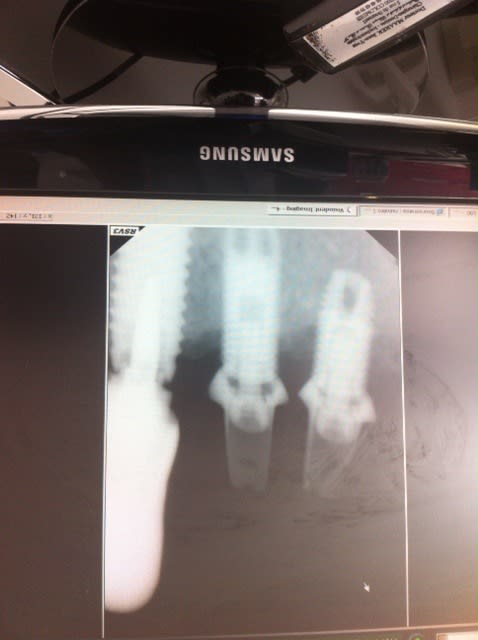

1/ des images en jpeg exportées du logiciel d'imagerie ou des captures d'écran à l'aide du logiciel capture de windows (selon la version) ou d'un petit logiciel gratuit qui s’appelle capturino stp car là c'est très mauvais comme rendu avec le smartphone...

2/ à première vue comme çà, çà colle assez bien avec des zimmer...dont le col est pété...mais j'attends de voir des images plus nettes pour me prononcer...;-)

amha, c'est du tout bon à mettre à la benne...semblerait qu'il ne reste plus que le filetage interne...mais plutôt que les photos, déjà remet les radios comme il faut tel que je te l'ai dit...çà sera bien plus net et çà me permettra d'analyser ces implants dans le détail...

+1 radio moche...les implants aussi

Il y a moyen de bien faire avec simple une capture d'écran, soit avec un iPhone, soit avec un Canon + 100 mm macro (pas de flash), mais faut que la radio originale soit OK...

sinon, exporte le fichier original

Ci joint en faible résolution, mais lisible,des radio via capture d'écran au Iphone 4S, faut aussi recadrer l'image, en 10 secondes sur le iPhone, et prendre la photo perpendiculaire à l'écran.